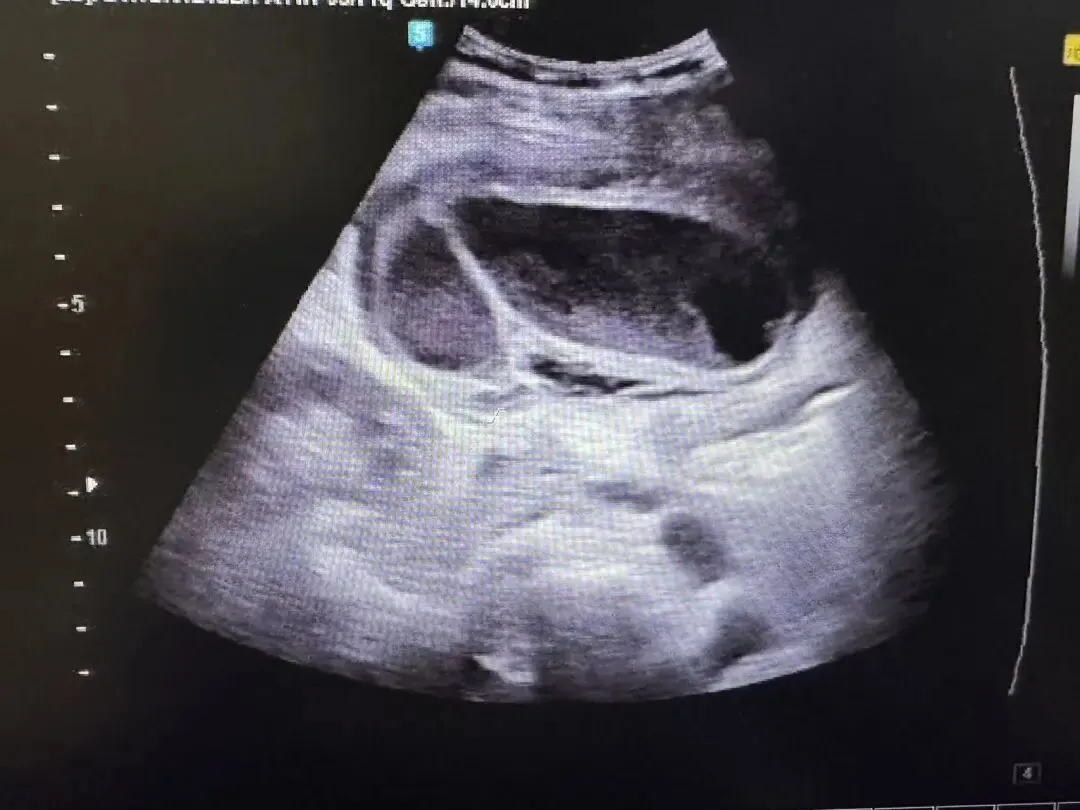

充填型胆囊结石

● 胆囊内胆汁较少或无胆汁,胆囊腔的无回声区消失,胆囊无正常的轮廓或形态,声像图仅表现为胆囊前壁呈弧形或半月状的强回声带,后方伴较宽声影,致使胆囊后壁不显示。

● 囊壁结石声影三联征(WES征:wall-echo-shadow征):前方为增厚胆囊壁的弱回声包绕中间结石的强回声,后方伴有声影。